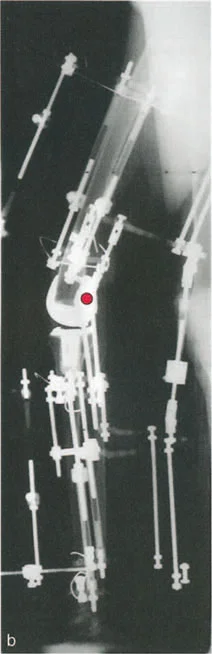

أمثلة أخرى رئيسية للتشوهات الديناميكية تشمل "الورم الفخذي المفرط" (Severe Femoral Anteversion) و "الورك الأفحج" (Coxa Vara). في كلتا هاتين الشذوذات المعمارية، يتم تقصير الطول الفيزيائي لذراع الرافعة لعضلات المبعدة (Abductor muscles) بشكل مرضي بسبب التشوه العظمي نفسه. قد تكون عضلة الألوية الوسطى (Gluteus Medius) صحية تمامًا، ومعصبة جيدًا، وقادرة على توليد قوة بيولوجية طبيعية، لكنها تعاني من خلل وظيفي سريري عميق لأن ميزتها الميكانيكية قد سُلبت بسبب الهندسة الهيكلية المتغيرة. هذه الفئة الفرعية المحددة من الأمراض تُعرف باسم "تشوه في طول ذراع الرافعة".

في حين أن التشوهات الديناميكية تُناقش غالبًا في سياق أمراض الأعصاب والعضلات لدى الأطفال، فإن المبادئ البيوميكانيكية التي تحكمها تنطبق عالميًا على إعادة بناء العظام لدى البالغين. يشمل ذلك سيناريوهات إعادة البناء المعقدة للغاية، مثل استبدال مفصل الركبة الكلي (TKR) واستبدال مفصل الورك الكلي (THR) المرتبطة بالانحرافات الشديدة خارج المفصل. إن فهم الأذرع الرافعة هو المتطلب الأساسي لإتقان هذه التقنيات المتقدمة في جراحة المفاصل وقطع العظم، وهو ما يتقنه الأستاذ الدكتور محمد هطيف في ممارسته اليومية.

- الورك الأفحج (Coxa Vara): تشوه خلقي أو تطوري في عظم الفخذ يؤدي إلى تقصير ذراع الرافعة لعضلات الورك المبعدة، مما يضعف قدرتها على تثبيت الحوض.

- الأشعة مع تحمل الوزن (Weight-bearing X-rays): تُظهر كيف تتصرف المفاصل والعظام تحت الضغط الطبيعي للجسم، وهو أمر حيوي لتقييم التشوهات الديناميكية.

- أشعة الأطراف الطويلة (Long Leg Films): تُؤخذ هذه الأشعة من الورك إلى الكاحل في صورة واحدة لتقييم المحور الميكانيكي الكامل للطرف السفلي وتحديد أي انحرافات.

- التصوير المقطعي المحوسب (CT Scans): يوفر صورًا ثلاثية الأبعاد للعظام، وهو مفيد بشكل خاص لتقييم التشوهات الالتوائية (مثل الورم الفخذي المفرط) وتحديد موقع مركز دوران الانحراف (CORA) بدقة.